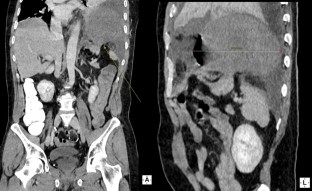

Fig. 1

Fig. 2